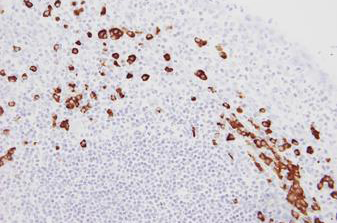

Rhabdomyosarcoma stained using FOXO1 (13q14) Break – XL for BOND (KBI-XL016).

The FOXO1 (13q14) Break - XL for BOND FISH probe detects genomic translocations involving the FOXO1 gene. FOXO1 (13q14) Proximal - XL and FOXO1 (13q14) Distal - XL are optimized to detect genomic regions proximal and distal to break points in the FOXO1 gene region.

When combined, both probes are used to detect translocations involving the FOXO1 gene at 13q14.